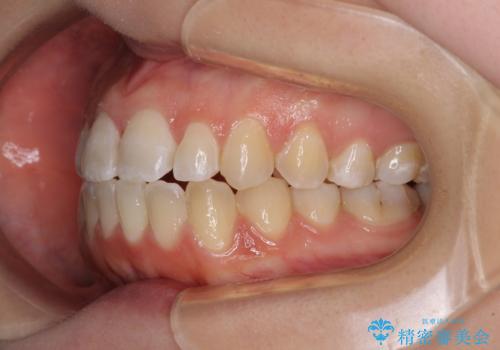

- 前歯の上下スペースによる食べにくさを気にして来院された患者様です。

インビザラインにより上下の前歯の隙間を閉じていくこととしました。

前歯のデコボコの解消と並行して上下の奥歯を圧下させるようにすることで、前歯を接触させるように計画しました。

上下の隙間に舌が入り込むことがオープンバイトの原因であったため、舌の筋肉のトレーニングも並行して行い、後戻りの抑制を図りました。